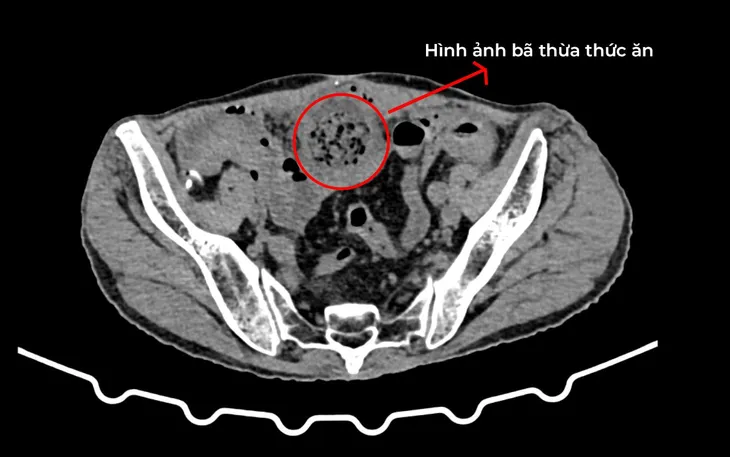

Kết quả chụp CT-Scanner ổ bụng cho thấy nhiều quai ruột non giãn, đường kính ngang lớn nhất khoảng 38mm, có mức nước - hơi. Đồng thời phát hiện một đoạn ruột non dính sát thành bụng, phía trên có ứ đọng bã thức ăn, xung quanh có dịch dày khoảng 20mm kèm thâm nhiễm mỡ; đoạn ruột non phía xa bị xẹp.